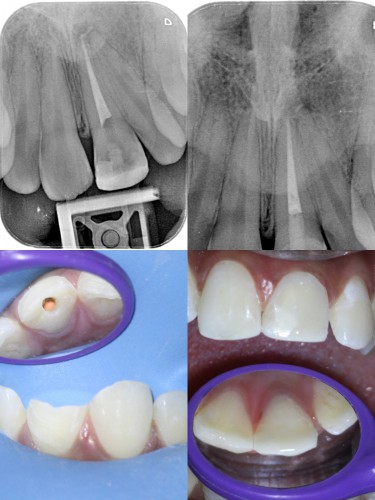

Pt 17yrs male presented with pain and discoloration of #9. After the Access prep,cleaning and shaping , temporary composite restoration was done. After 2 visits of CAOH dressing obutration completed and bleach placed for a week. Composite resoration done in #8 and repeated in #9.